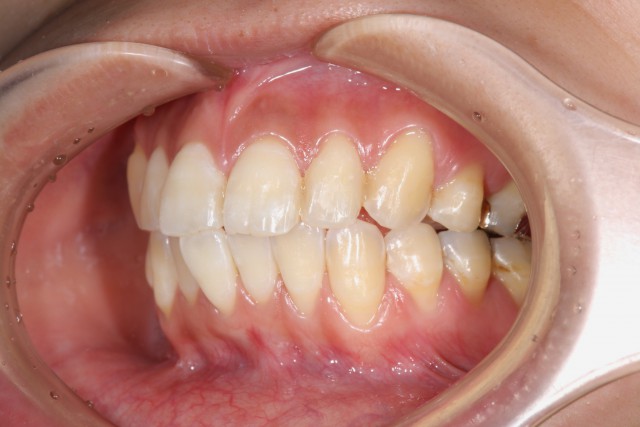

施術後

金属アレルギー対策はもちろんですが、口をあけたときにも金属が目立つということがないので非常に美しいです。口腔内の金属は歯ぎしりの原因となっているということもあります。たとえば髪が抜けやすくなった、肌にブツブツが出来やすいなどの症状などは金属アレルギーかも知れません。一度病院でアレルギー検査を行うことをおすすめします。